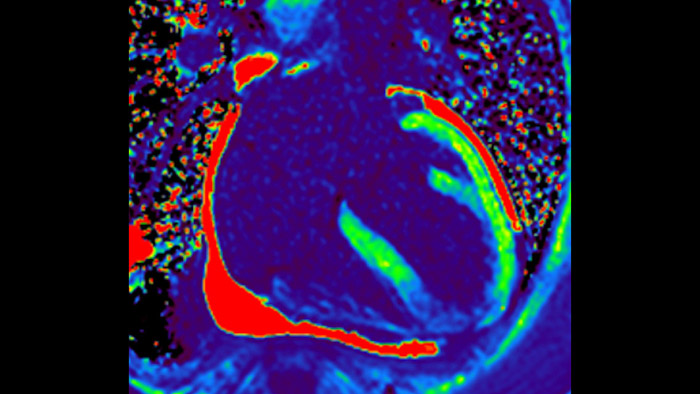

IntelliSpace Portal MR CaaS5,6 Strain7 supporta nella diagnosi e nel monitoraggio dei pazienti fornendo parametri globali di strain, quali strain longitudinale globale (GLS), strain circonferenziale globale (GCS) e strain radiale globale (GRS), utilizzando immagini RM in asse corto e lungo e descrivendo inoltre la deformazione del miocardio, come il suo accorciamento, ispessimento e allungamento durante il ciclo cardiaco.

La diagnostica odierna spesso non è in grado di rilevare le disfunzioni cardiache fino a quando non si manifestano sintomi. MyoStrain valuta la deformazione del miocardio in 48 segmenti cardiaci e fornisce ai medici uno strumento diagnostico utile per identificare con anticipo la disfunzione funzionale prima che il cuore nel suo complesso sia compromesso.

La diagnostica tradizionale non offre la visibilità necessaria per vedere gli effetti di un trattamento cardiaco o individuare disfunzioni prima che si verifichino i sintomi. Combinando la sequenza di acquisizione MRI Fast-SENC di Philips con lo strumento di analisi MyoStrain di Myocardial Solutions, i lievi cambiamenti precoci nella funzione cardiaca possono essere misurati direttamente.